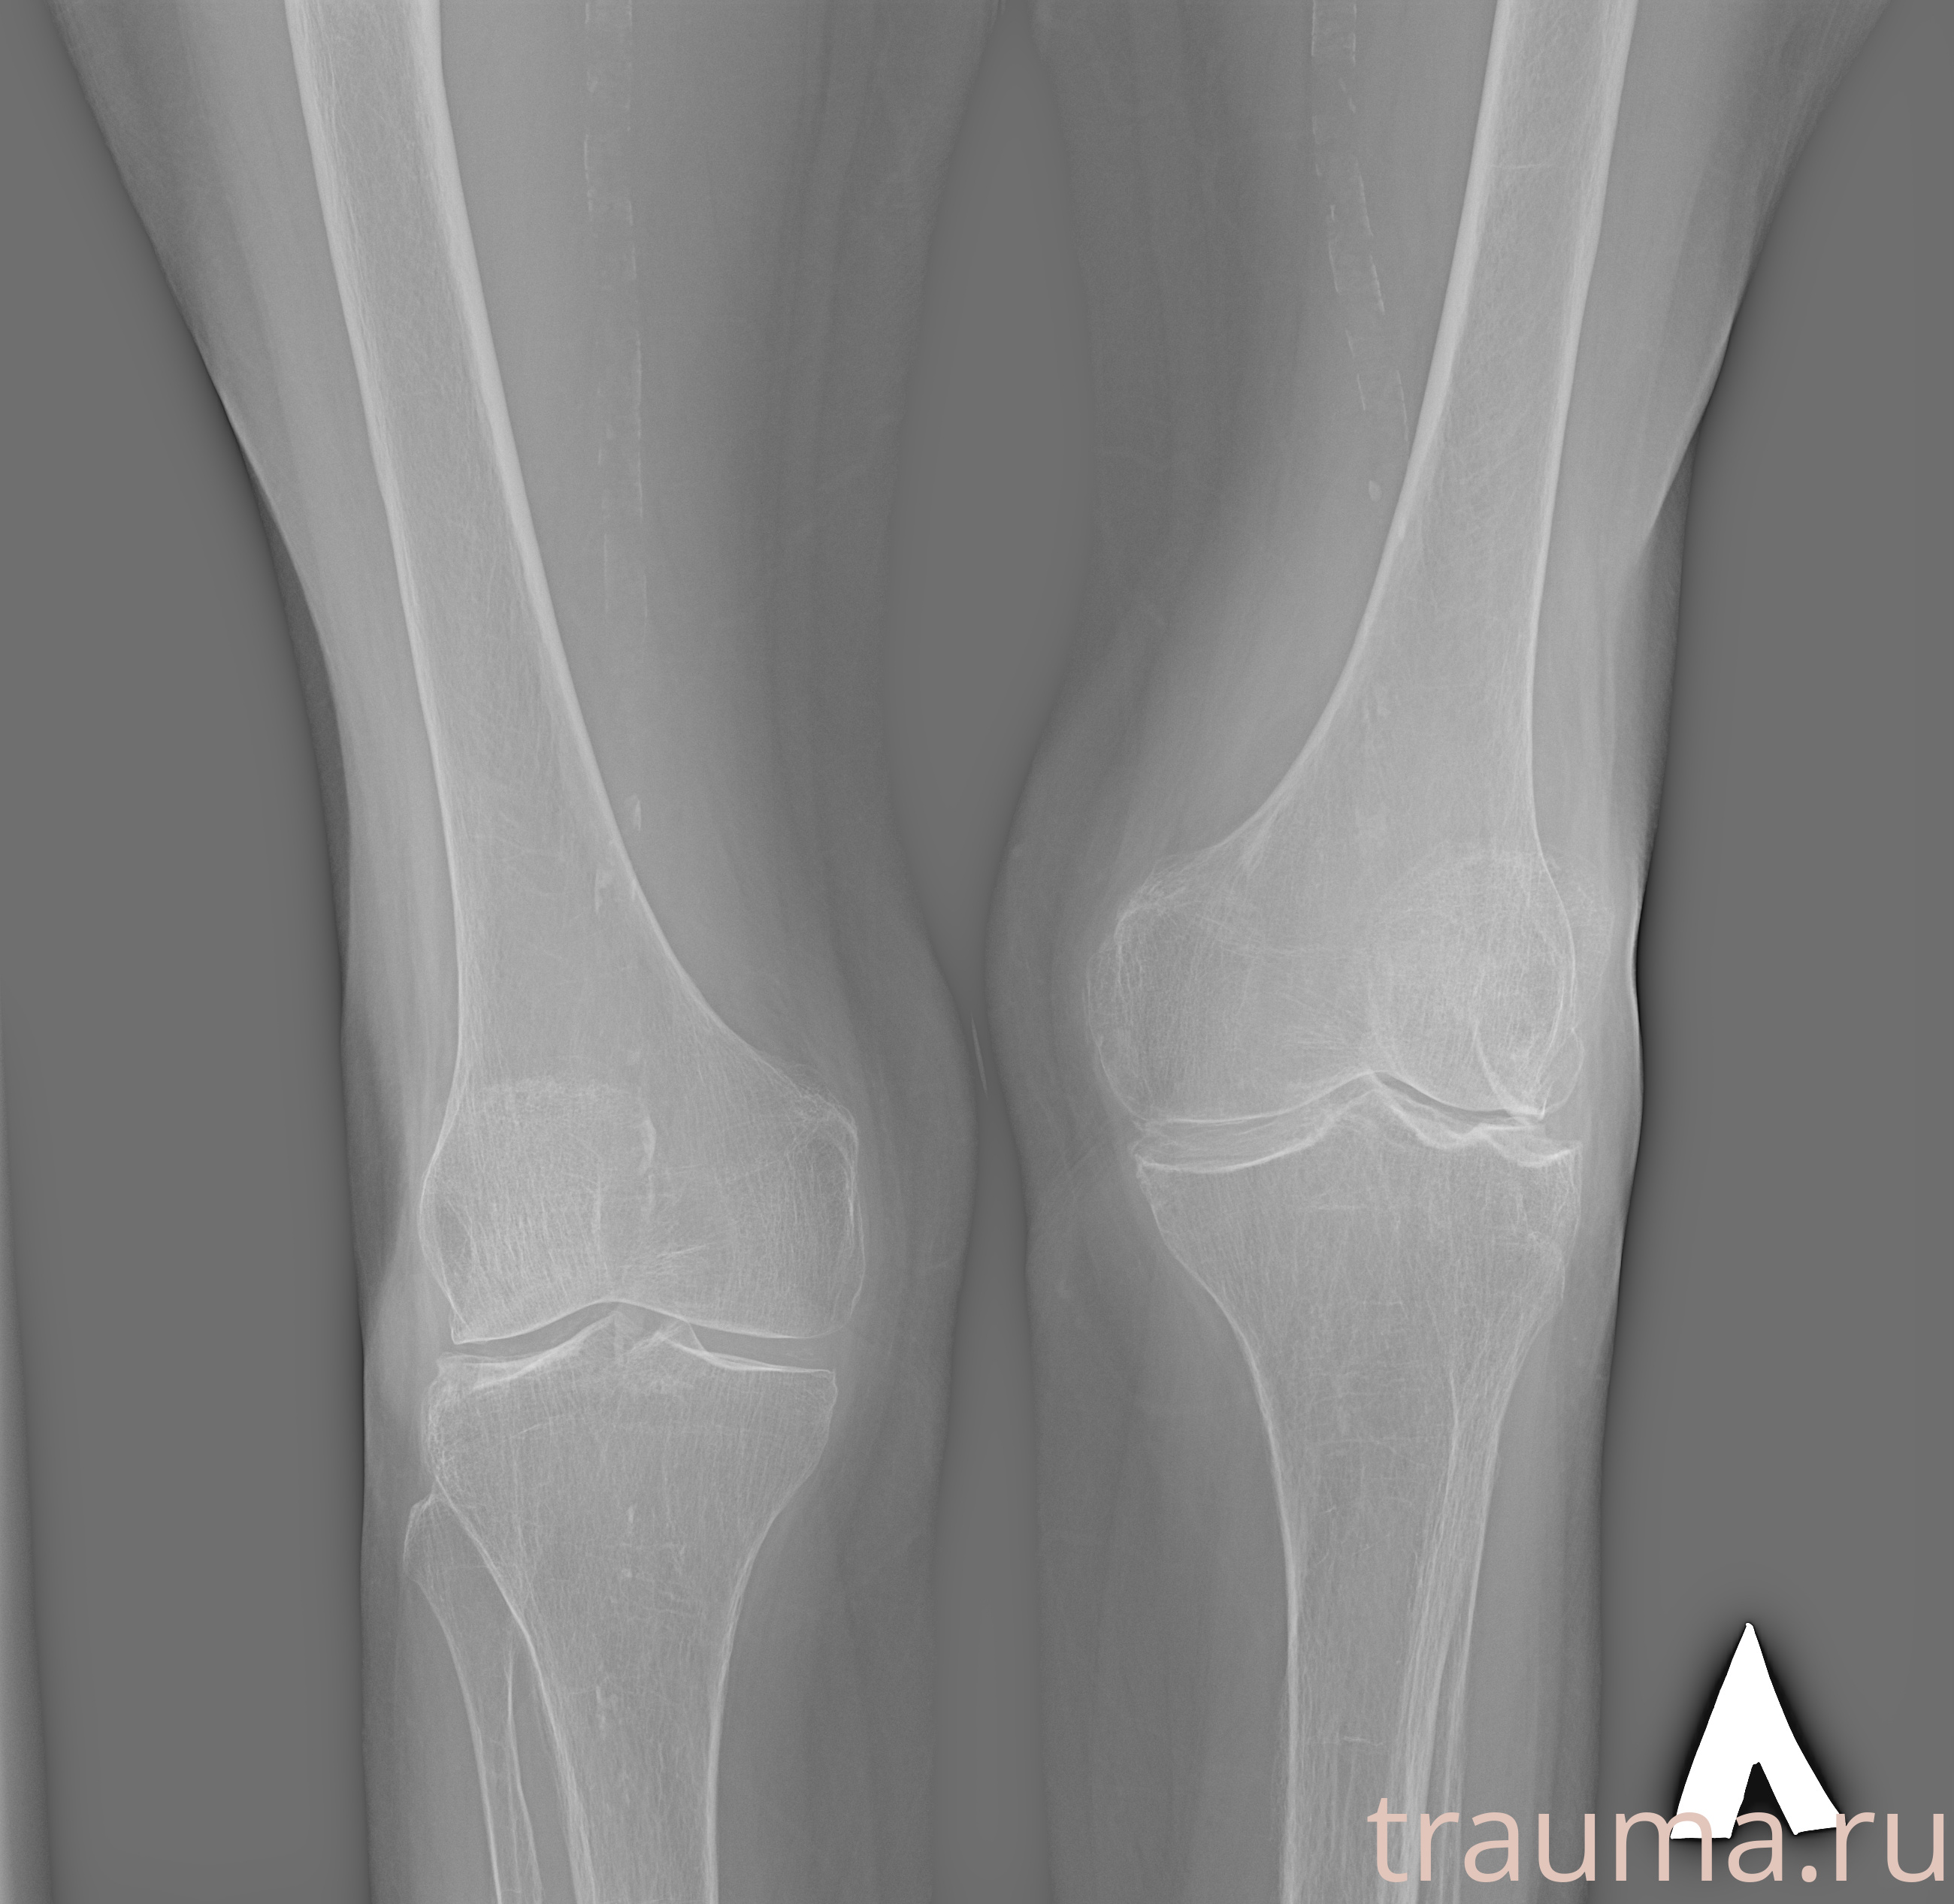

Рентген на дому: по вашему адресу приезжает врач-рентгенолог, травматолог-ортопед с мобильным рентгеновским аппаратом, проводит диагностику травмы или заболевания, делает необходимые рентгенограммы, дает рекомендации по дальнейшему лечению. Получить качественные снимки в домашних условиях возможно благодаря уникальной методике, разработанной МосРентген Центром для института  Склифосовского